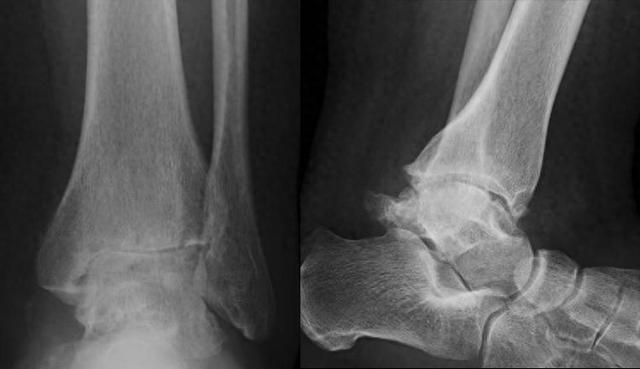

术前X线显示踝关节间隙消失,软骨下骨硬化,大量骨赘形成